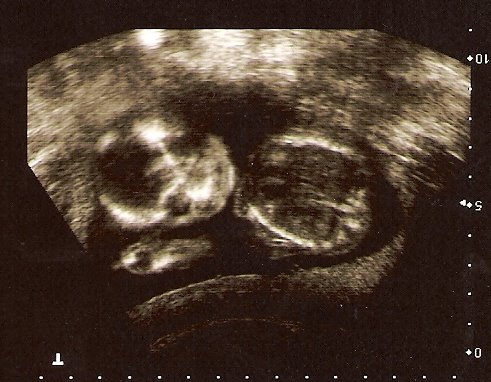

Here are the sono pics from today

Aww, it looks like he's waving in the first pic--lol

ETA: Or flipping us the bird--LOL

That first shot is really cute, it looks like he is smiling!!